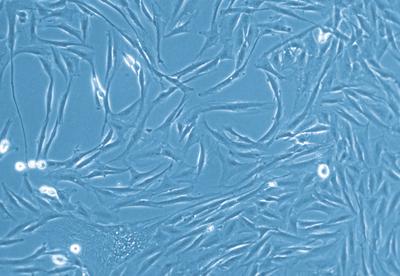

HUF Pellet: Pellet from Human Uterine Fibroblasts, 1 million cells^